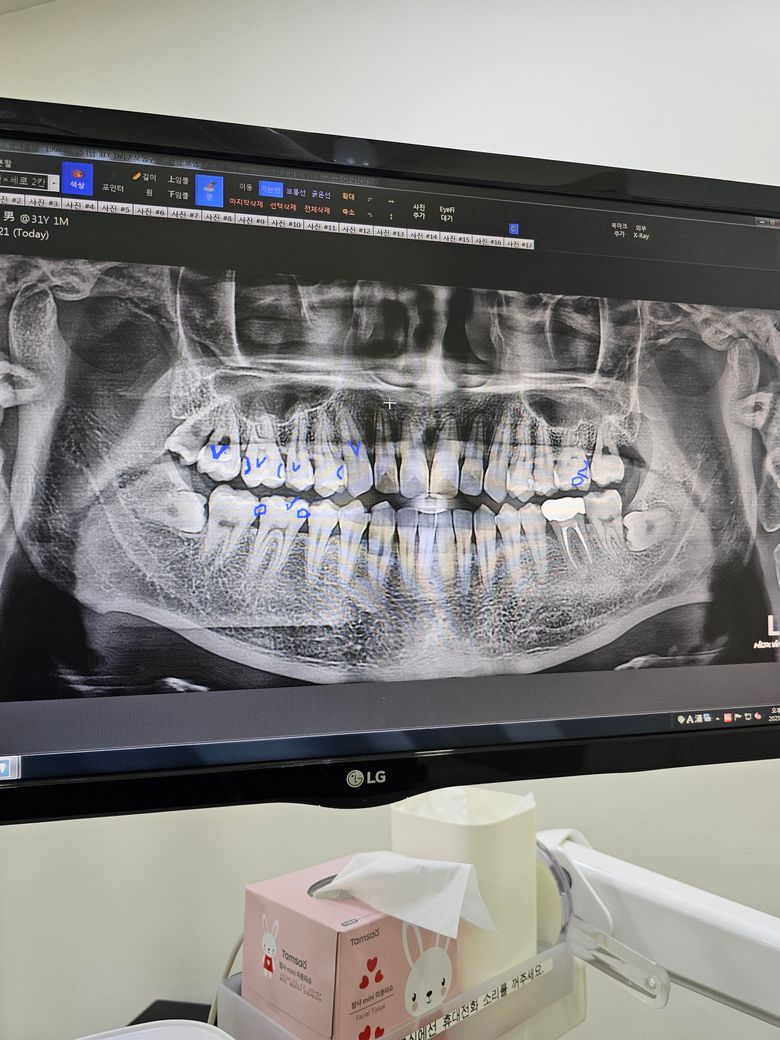

• 4번 째 사진

두번째 치과에서 하신 말씀이랑 다들 비슷한 의견일꺼에요. 치과의사마다 치료 하는 방법이 다르기 때문에 어떤게 옳다고 말씀드리기가 어렵습니다. 사진상으로 인접면에 충치가 없는건 아니고 의심되는 치아들이 많이 보이긴하니 계속해서 의심이 드신다면 불편한 치아만 치료를 먼저 하시고 나머지는 지켜보시면될것같습니다.

1. 진단과 관련해선 확인을 원하신다면 대학병원 보존과 내원을 한번 해보시는 것도 좋습니다.

2. 옆면 충치에 대해 인레이, 레진, 크라운을 어떻게 할지는 치과의사의 가치관에 따라 다릅니다. 꼭 뭐가 맞다 이렇게 정해진 건 없습니다.